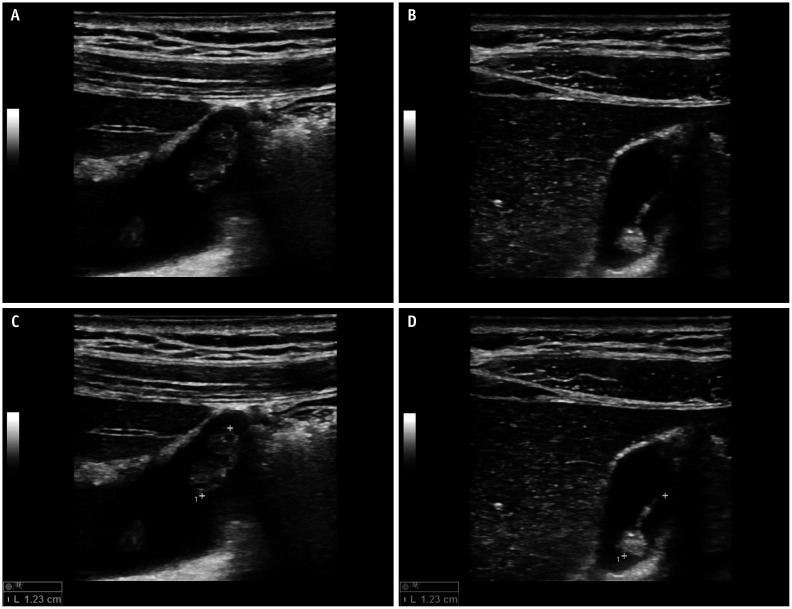

Abstract Image